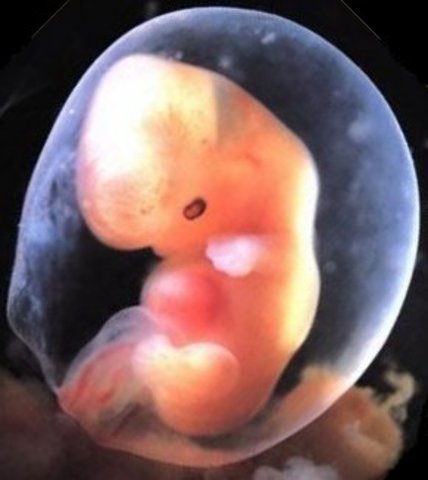

• Week Five: The Embryonic Stage Begins

Week Five: The Embryonic Stage Begins

The Placenta is starting to develop. The embryo recieves oxygen and nutrients through the placenta.

• Week Six: The Heart Begins to Beat

Week Six: The Heart Begins to Beat

Blood vessels and blood cells start to develope and a pipe shaped heart starts to form and beat. The brain is also divided into five parts.

• Week Seven: Arms and Legs Begin to Grow

Week Seven: Arms and Legs Begin to Grow

The baby's main organs are starting to developed as well as their arms and legs. The heart has now been divided into two chambers.